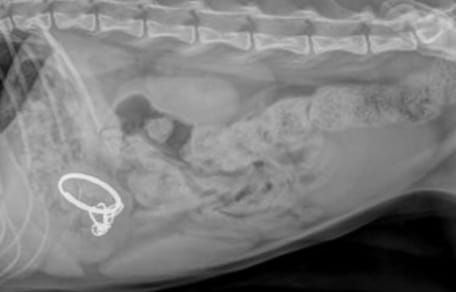

Haru the cat's X-ray

© Tierheim Duisburg / Facebook

Haru was rushed to the veterinary clinic for an X-ray.

When the vets examined the image, they turned pale. The cat's stomach contained more sharp pieces from the broken device. He was at risk of an intestinal blockage, which could lead to an agonising death.

Even more shockingly, the vets discovered that Haru must have swallowed the laser pointer before he even arrived at the shelter, which was at least ten days earlier. For ten days, he had carried these dangerous fragments inside him without a single complaint.